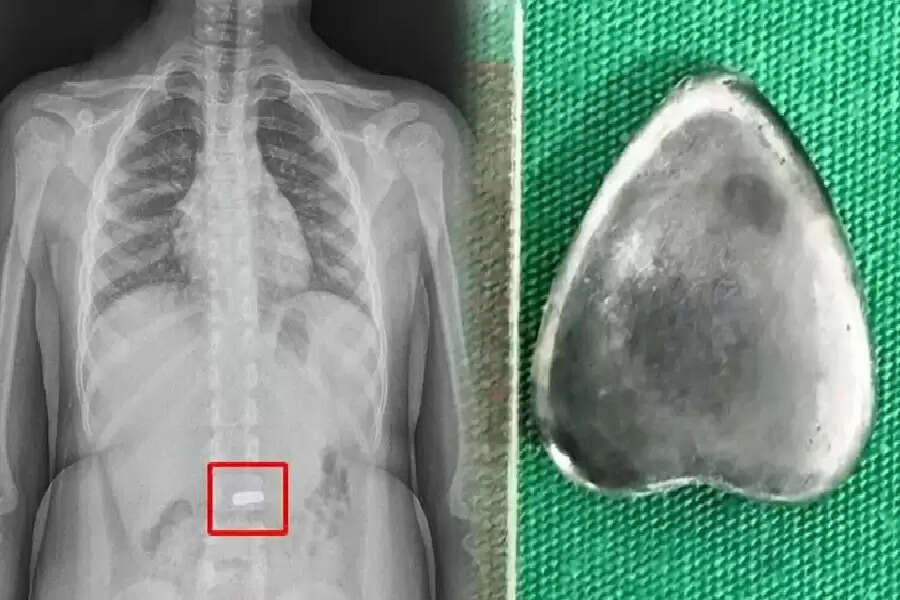

वियतनाम में एक अजीबोगरीब मामला सामने आया है। डॉक्टरों ने छह साल के एक बच्चे के पेट से दिल के आकार का एक चुंबक निकाला। दोपहर के भोजन के बाद खेलते समय, बच्चे ने गलती से 2 सेंटीमीटर लंबा चुंबक निगल लिया। सौभाग्य से, उसके माता-पिता ने बच्चे को चुंबक निगलते हुए देख लिया और उसे तुरंत पास के अस्पताल ले गए। डॉक्टरों ने एक्स-रे लिया तो पाया कि यह मरीज की आंतों में फंसा हुआ था। चूँकि इससे आंतों में छेद और नेक्रोसिस होने का खतरा था, इसलिए एंडोस्कोपी के ज़रिए चुंबक को तुरंत निकाल दिया गया। वियतनाम के विन्ह लॉन्ग स्थित शुयेन जनरल अस्पताल की मेडिकल टीम ने यह सर्जरी सफलतापूर्वक की।

बच्चे को बिना किसी चोट के देखभाल की गई। बताया जा रहा है कि ऑपरेशन के बाद उसी शाम उसे छुट्टी दे दी गई। वहाँ कार्यरत डॉक्टर ने कहा, "मरीज़ को जल्दी अस्पताल लाया गया था। इसलिए हम जल्दी ऑपरेशन कर पाए। चूँकि वस्तु नुकीली नहीं थी, इसलिए शरीर पर कोई चोट नहीं आई। खून भी नहीं निकला। अगर वस्तु लंबे समय तक अंदर रहती है, तो पाचन तंत्र को गंभीर नुकसान पहुँचने की संभावना थी।